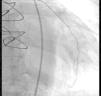

Considering the patient's ischemic burden, new-onset biventricular systolic dysfunction, and the absence of signs of pulmonary embolism, and as she was clinically stable after three days, it was decided to perform cardiac magnetic resonance imaging (MRI), which showed slight left ventricular systolic dysfunction, right ventricular dilatation with severe systolic dysfunction and transmural late enhancement in the mid-apical segments of the right ventricle, highly suggestive of RVI (Figures 3 and 4). Pulmonary artery angiography showed no signs of pulmonary thromboembolism. In this non-linear clinical case cardiac MRI was sufficiently informative to enable a diagnosis to be made: RVI.

The patient's clinical deterioration with acute decompensated heart failure in spite of therapy, including revascularization, fluid resuscitation and inotropic support, was a warning that further investigation was required. Cardiac MRI provided a more conclusive study of ventricular function and wall motion abnormalities, and gadolinium late enhancement demonstrated that the ischemic region was in the right apical ventricular wall. Cardiac MRI is the most sensitive method to assess right ventricular function. Right ventricular involvement usually occurs in the inferior segments and the apex of the right ventricle, regions in which imaging of wall motion abnormalities with echocardiography is particularly challenging.8 Most reports do not specify an optimal timing for MRI in an acute setting, and each situation calls for different timings.